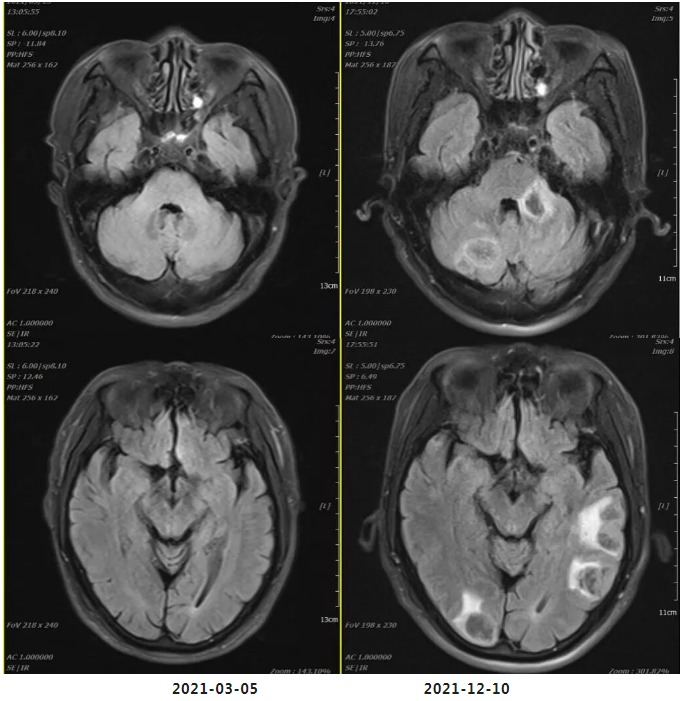

2021年12月11日疗效评价:PD(两肺及胸膜结节明显增多、增大;纵隔前间隙、纵隔内及两肺门转移淋巴结(现约4.7×3.5cm)较前增多、增大,上腔静脉、左头臂静脉受累狭窄;双侧小脑半球、大脑半球转移(约2.1×1.7cm)新发。